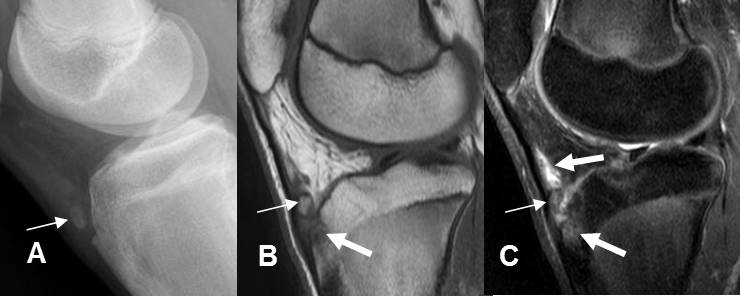

Fig 200. Enfermedad de Osgood Schlatter.

A: Rx lateral, B: RM sagital en T1 y C: RM sagital en STIR. Fragmentación de la espina tibial anterior. (Flechas delgadas). En las imágenes de RM hay cambios inflamatorios en la parte anterior de la tibia y la grasa de hoffa.(Flechas gruesas).